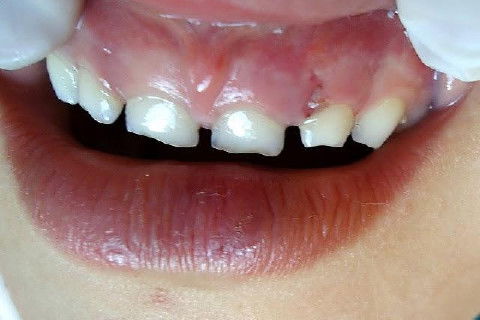

Menino de 6 aninhos sofreu um traumatismo ontem na hora do recreio, lá na escolinha aonde atendo, bateu a boquinha na mesa na hora do lanche.

Examinei-o e constatei ter sofrido apenas uma concussão.

CONCUSSÃO é o trauma dentário menos agressivo que se apresenta.

Sem consequências aparentes ao exame clínico, nenhum dano ao tecido dentário, com pequena agressão aos tecidos de suporte e os dentes apresentam pequena sensibilidade ao toque.

Obs: As duas últimas fotos foram tiradas hoje (24 hs depois).

Fotos do caso